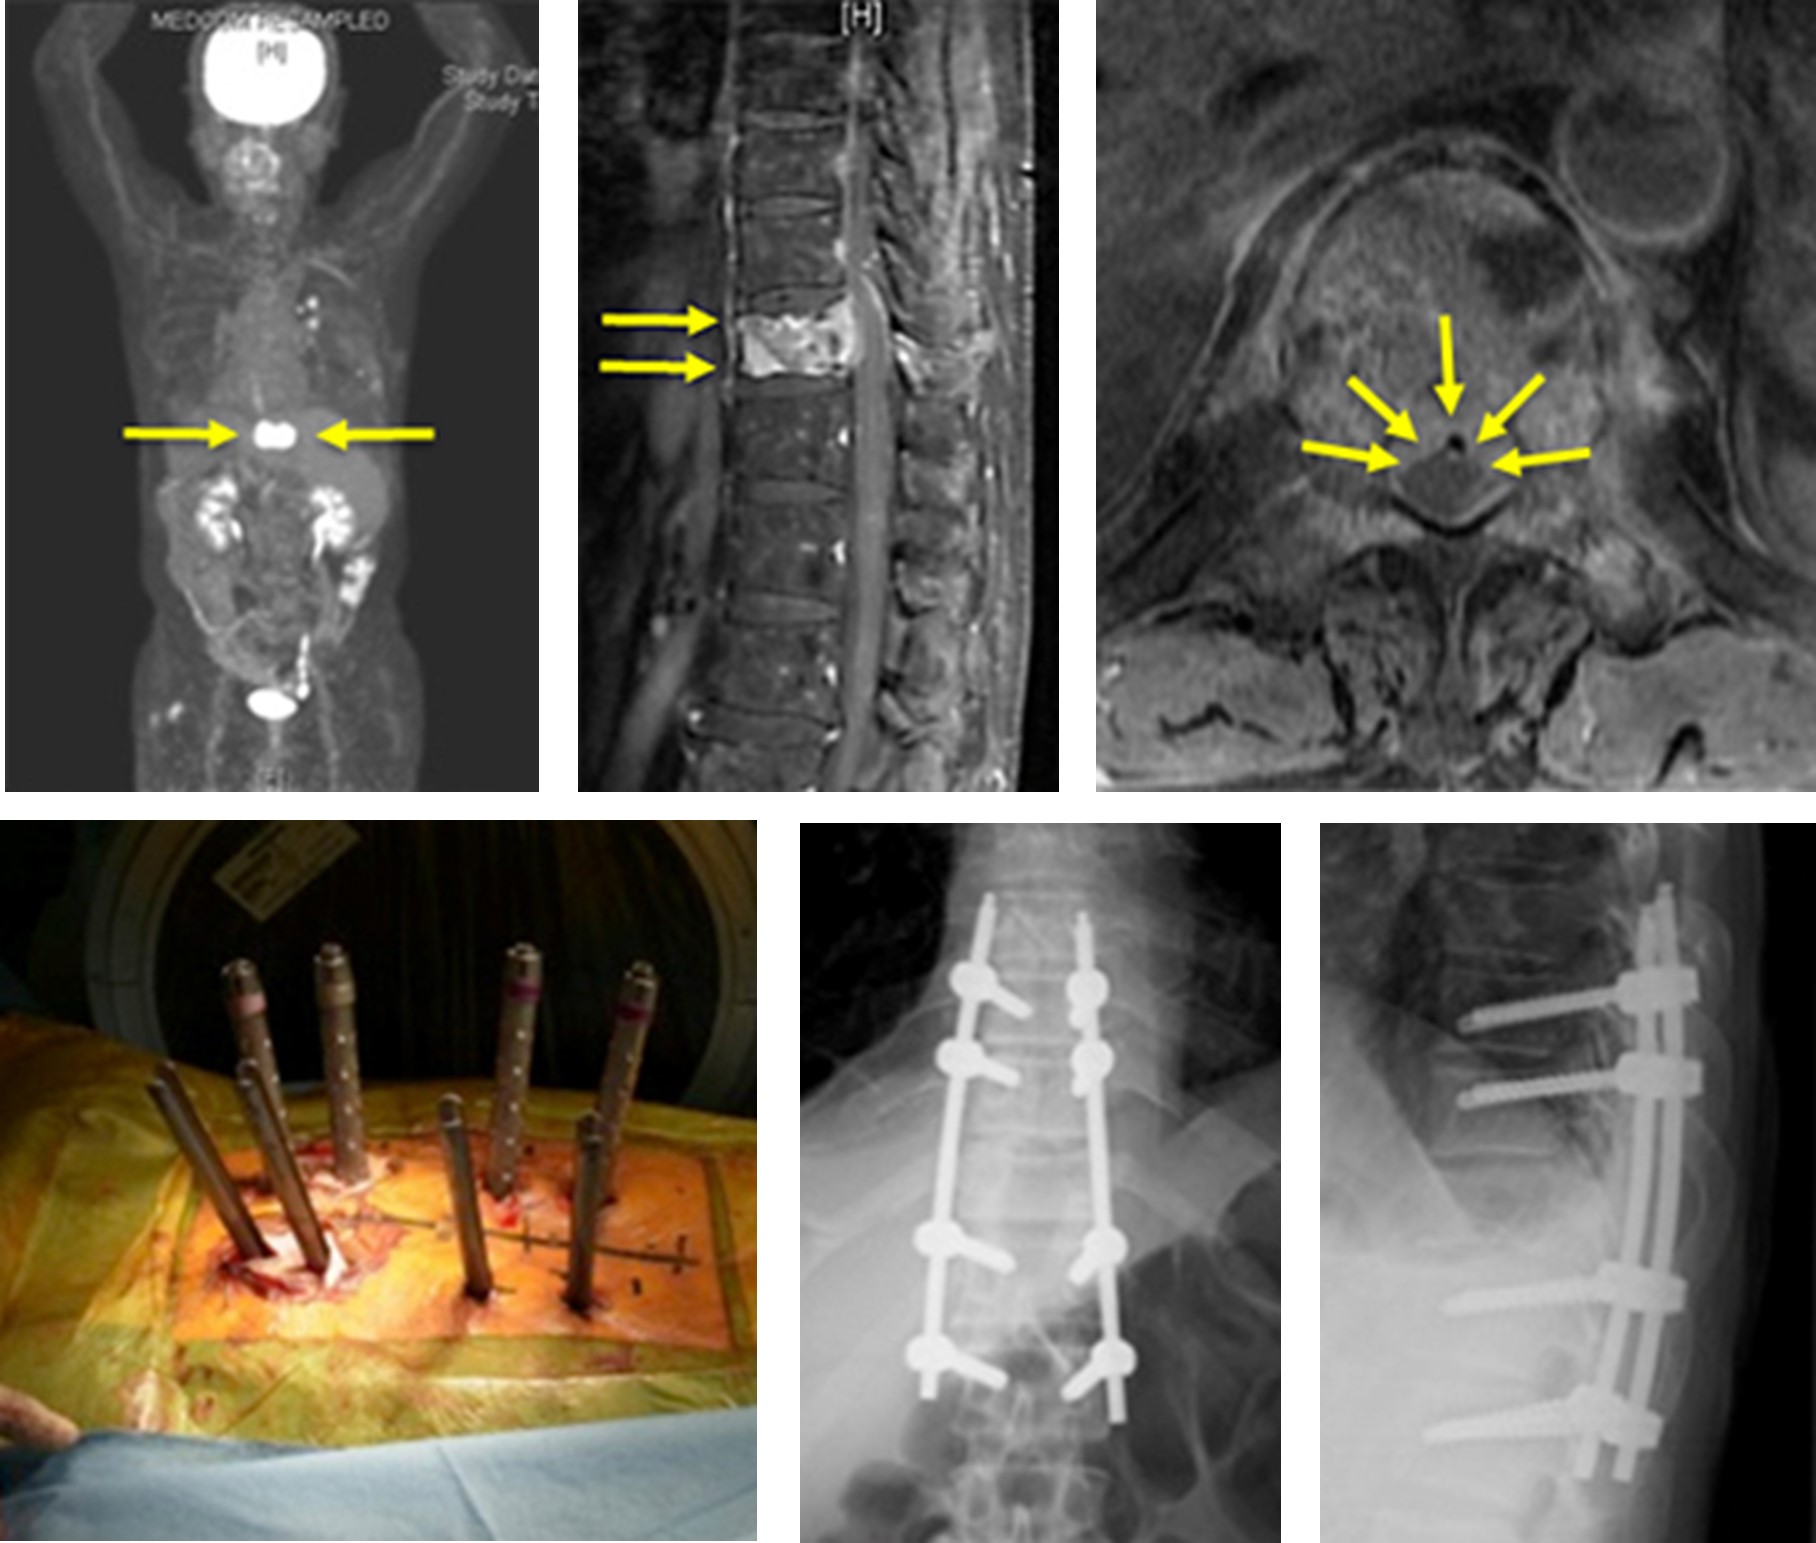

【転移性てんいせい脊椎せきつい腫瘍しゅように対するミスト手術】

転移性脊椎腫瘍による麻痺や痛みで苦しんでいる患者様の苦痛を少しでも軽減するために最小侵襲脊椎手術を行っています。従来の切開手術に比べ、術中・術後の出血量が少なく、輸血率も少ないことが証明されております。身体に対する負担が少ないために術後早期のリハビリテーションや放射線治療が可能です。

図 上)MRIで造影効果のある脊椎が描出されています。本症例では、がんの既往があり、同部位は転移性脊椎腫瘍と診断されました。椎体が破壊され、腫瘍が脊髄を圧迫しています。

(下)本症例では、従来のように大きな切開を加えること無く、ミスト手術と呼ばれる経皮的椎弓根スクリューを用いた特殊な方法で、小さい皮膚切開で脊椎を安定化しました。がんの患者様に対しては、できるだけ体にかかる負担の少ない低侵襲な方法が望ましいと考えています。